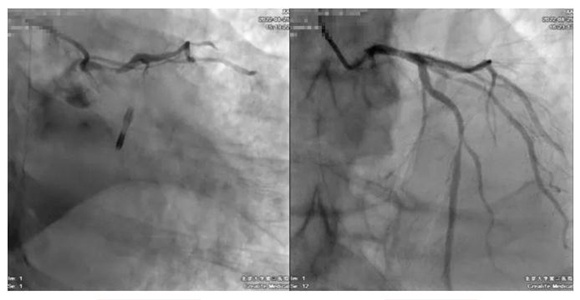

急诊抢救室的医护人员立即进行抢救,并迅速将患者送至心导管室,韩江莉、何立芸立即为患者植入主动脉内球囊反搏(IABP)维持循环,并行冠状动脉造影,证实了给心脏供血最重要的主干道——冠状动脉的左主干几近闭塞。患者反复室颤,病情极不稳定。介入团队在心外按压、反复多次电除颤、气管插管、呼吸机支持下为患者精准实施了左主干支架植入,打通了生命主干道。

左主干次全闭塞 左主干开通后